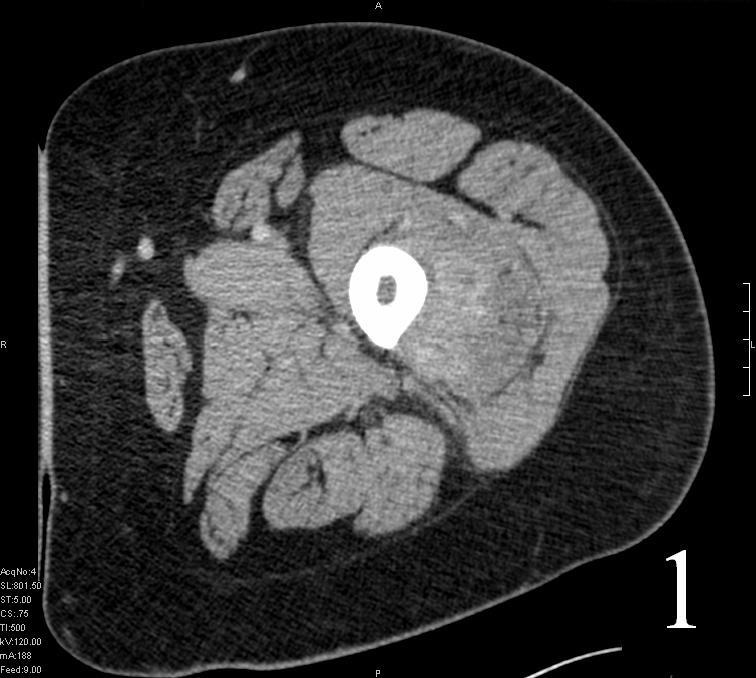

CT

• Shows attenuation similar to the muscle

• May be heterogenous with areas of necrosis and hemorrhage

Fig. 1

Fig. 2

Fig. 1-2 Axial (Fig. 1) and coronal CT (Fig. 2) reconstruction of the femur and thigh shows an Extraskeletal Ewing Sarcoma arising in the soft tissues adjacent to the femur